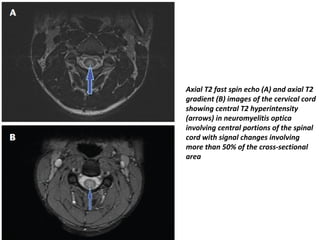

• Spinal cord involvement is extensive, with high T2

signal extending over long distances (over three or

more vertebral segments, often much more - this is

known as a longitudinally extensive spinal cord lesion) .

• Also helpful in distinguishing it from MS demyelination

is the involvement of the central part of the cord (MS

lesions tend to involve individual peripheral white

matter tracts).

• Imaging features acutely include:

– T1: hypointense

• follow-up scans may demonstrate cord atrophy and low T1 signal

– T2: hyperintense

• (>3 vertebral body length of involvement) with involvement of the

central grey matter

– T1 C+ (Gd)

• patchy "cloud like" enhancement of T2 bright lesions may be

present

• Thin ependymal enhancement similar to ependymitis

• open ring enhancement is not a feature of NMO

Axial T2 fast spin echo (A) and axial T2

gradient (B) images of the cervical cord

showing central T2 hyperintensity

(arrows) in neuromyelitis optica

involving central portions of the spinal

cord with signal changes involving

more than 50% of the cross-sectional

area

Axial T2 fastspin echo (A) and axial T2 gradient (B) images of the cervical cord showing central T2 hyperintensity (arrows) in neuromyelitis optica involving central portions of the spinal cord with signal changes involving more than 50% of the cross-sectional area